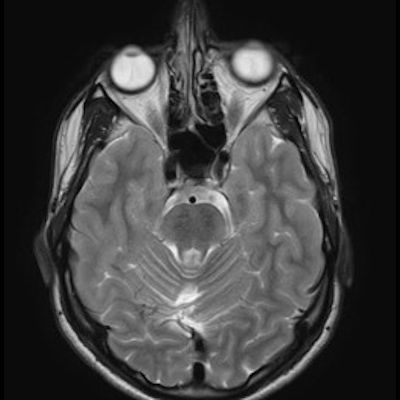

11 ay, Nöbet

Charlevoix-Saguenay Otozomal Resesif Spastik Ataksisi (ARSACS)

Charlevoix-Saguenay Otozomal Resesif Spastik Ataksisi ARSACS

ARSACS (Charlevoix-Saguenay otozomal resesif spastik ataksisi) Sendromu

ARSACS

Autosomal recessive spastic ataxia of Charlevoix-Saguenay

Serebellar folya sinapsisi